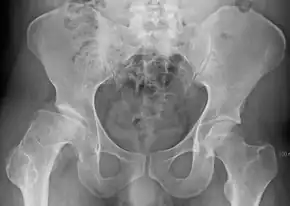

| Radiograph of a person with Legg–Calvé–Perthes disease | |

X-rays of the hip may suggest or verify the diagnosis. X-rays usually demonstrate a flattened, and later fragmented femoral head. A bone scan or MRI may be useful in making the diagnosis in those cases where X-rays are inconclusive. Usually, plain radiographic changes are delayed six weeks or more from the clinical onset, so bone scintigraphy and MRI are done for early diagnosis. MRI results are more accurate, i.e., 97 to 99% against 88 to 93% in plain radiography. If MRI or bone scans are necessary, a positive diagnosis relies upon patchy areas of vascularity to the capital femoral epiphysis (the developing femoral head).